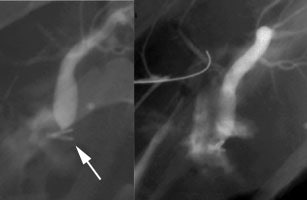

Bile Leak: This is another example of a bile leak. The hepatobiliary exam demonstrated pooling of tracer in the porta hepatis in this post-laparoscopic cholecystectomy patient. No bowel activity was appreciated. The percutaneous cholangiogram revealed that the common bile duct had been clipped (white arrow) at surgery. |